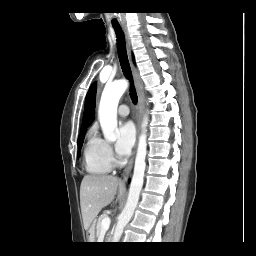

MUÑOZ BARRIENTOS, ANTONIO

1006289633

AUN100628

sábado, 22 de marzo de 2025

COLUMNA DORSAL Y LUMBAR AP Y LATERAL

11/Mar./2001

A QUIEN CORRESPONDA

AGS UNIVERSIDAD

9466, 9468